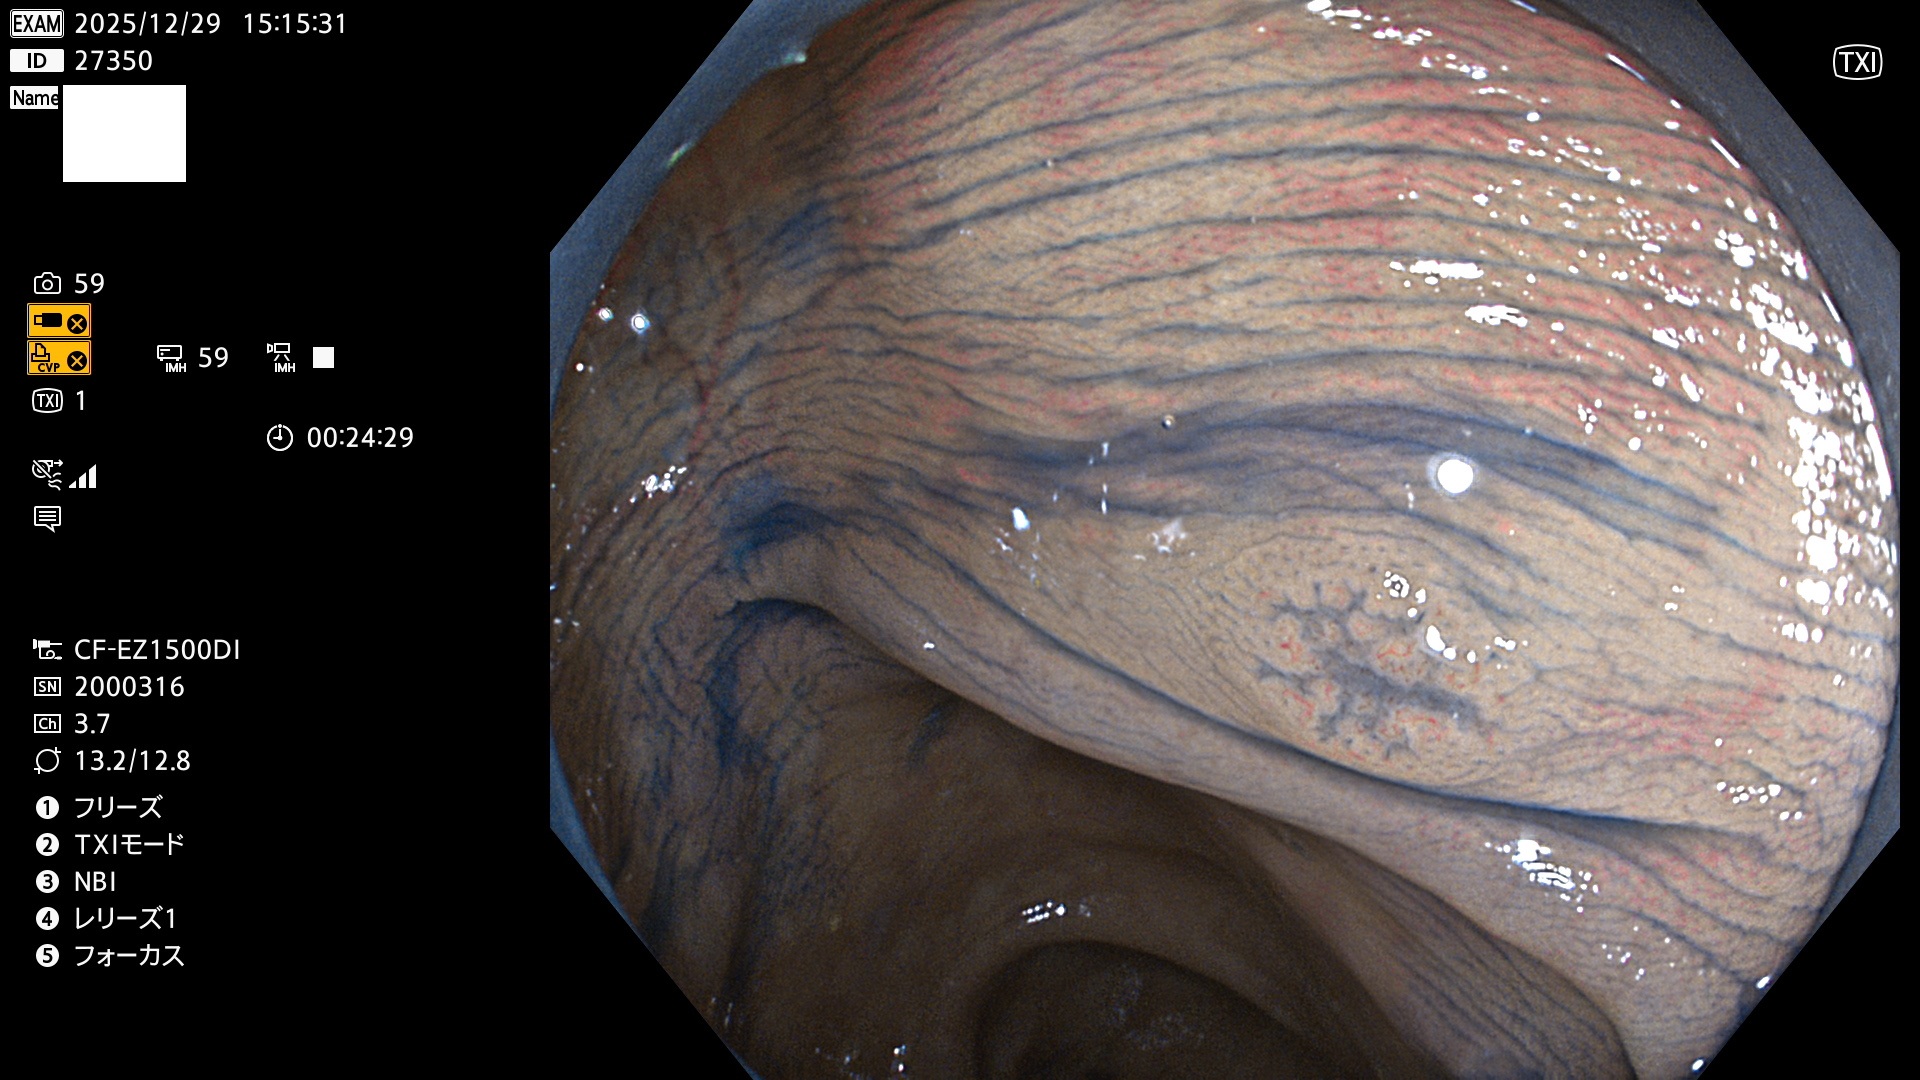

完全に平坦な物をUb、陥凹している物をUcと呼びます。Ubは認識が困難で、Ucはびらん(炎症)と紛らわしいために見落とされやすく、「内視鏡後・大腸癌」の原因になります。

毎週の検査(木・金・土・日)に発見されたUbとUc型・腺腫を、その週の日曜の夜にUPし1週間、提示します。

2025年12月18日〜12月29日の8日間(80件)13個 (Uc_ADR=13個/80人=16%)